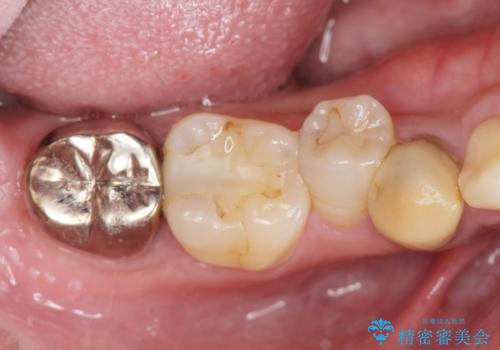

- 過去、多数の部位の虫歯治療を受けこれまで再発を繰り返してきたことから「徹底的な虫歯治療を受けたい。」と希望され来院されました。

虫歯の大きさから保存できなかった歯はインプラント治療を行い、その他の歯は虫歯のステージに合わせて根管治療、セラミックインレー、 セラミッククラウンを精密に行うことで長期的な予後を期待できる状態へと治療を進めます。